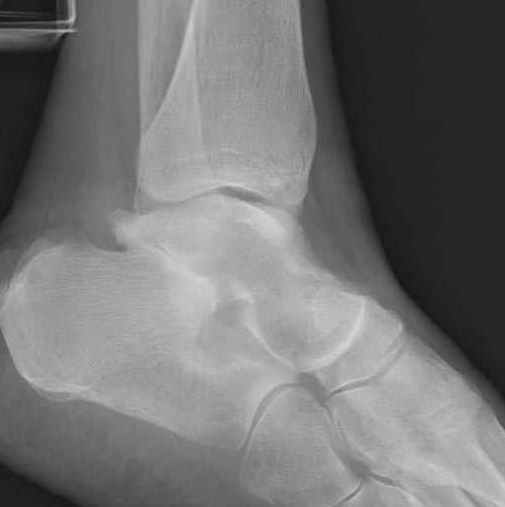

из

Уважаемые участники русского Ортофорума, поздравляю всех со всеми прошедшими праздниками: Новым годом, Рождеством, Hanukkah, Kwanzaa, желаю участникам всего наилучшего и здоровья. Повреждение таранной кости. Больной 81г автоавария, повреждение таранной кости, здесь снимки.

Какие рекомендации? Djoldas Kuldjanov, MD Department of Orthopedic Surgery St. Louis University Medical Center